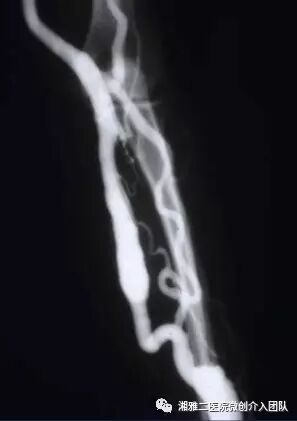

穿刺成功后行顺行性造影,了解狭窄的部位和程度

造影所见,可见无名静脉闭塞并侧枝形成

以上为再通过程